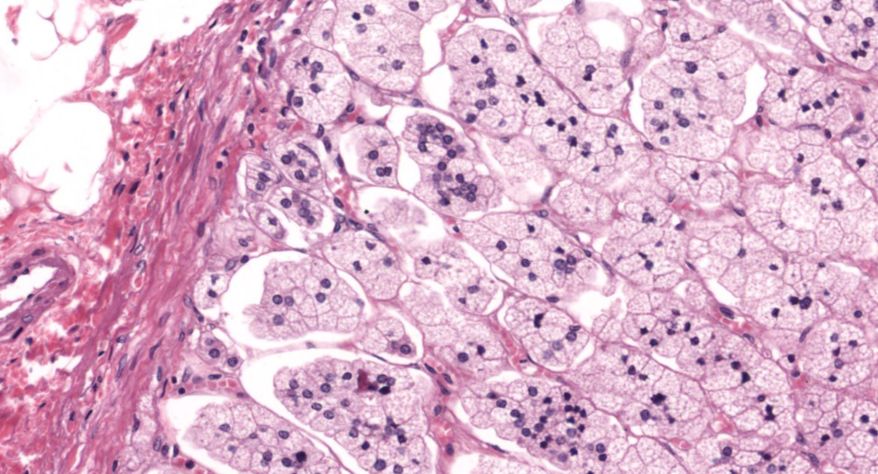

甲状腺

2.滤泡